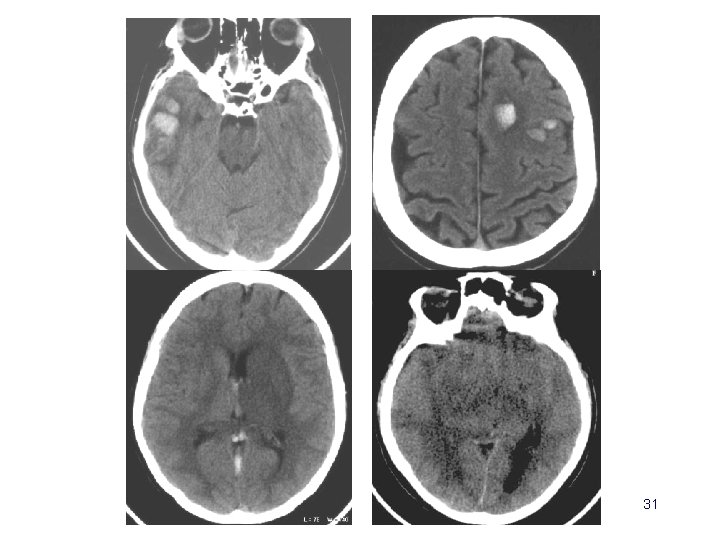

Scanner cérébral • Œdème cérébral – diffus ou localisé – seul ou associé • Discret effet de masse • Souvent décrit mais non spécifique – difficile à affirmer chez le sujet jeune – difficile à différencier d ’un infarctus veineux 29

Scanner cérébral • Infarctus veineux – hypodensité – effet de masse – prises de contraste • Infarctus hémorragiques – pétéchies … – Hématomes – HSA 30

31